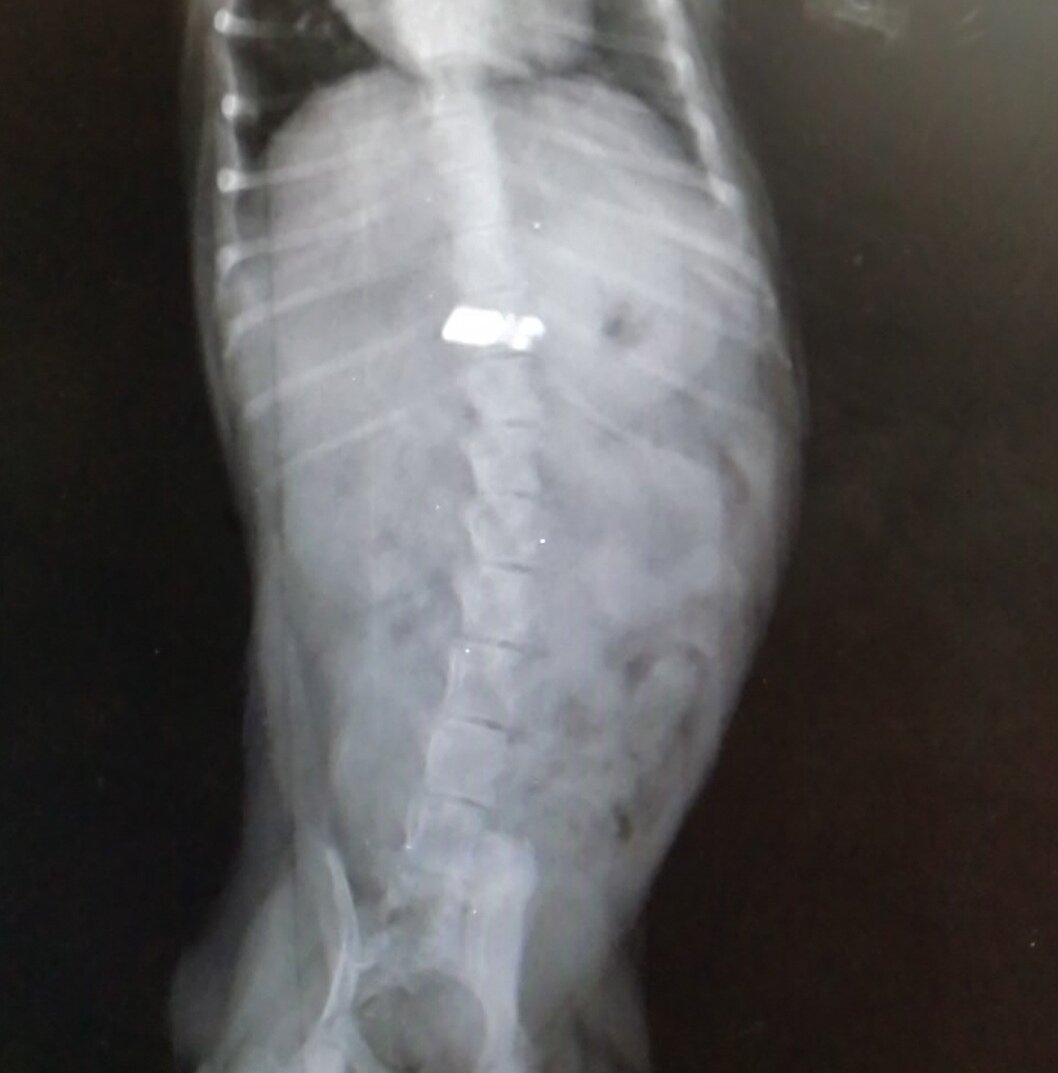

Наш сегодняшний герой- щенок тойтерьера. Активный, игривый и радующий своих владельцев.

Видимо в какой-то момент ему не хватило внимания и он решил сгрызть все провода от гаджетов. А заодно и полакомиться частью всего этого добра.

Инородный регнтгенконтрастный предмет в области желудка

Малыша принесли на прием с рвотой. Рассказали всю предысторию, и конечно же мы сделали рентген. А там...